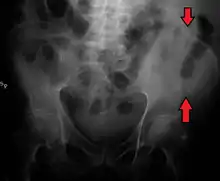

The crest of the ilium (or iliac crest) is the superior border of the wing of ilium and the superiolateral margin of the greater pelvis.

The iliac crest stretches posteriorly from the anterior superior iliac spine (ASIS) to the posterior superior iliac spine (PSIS). Behind the ASIS, it divides into an outer and inner lip separated by the intermediate zone. The outer lip bulges laterally into the iliac tubercle.[1] Palpable in its entire length, the crest is convex superiorly but is sinuously curved, being concave inward in front, concave outward behind.[2]

The top of the iliac crests also marks the level of the fourth lumbar vertebral body (L4), above or below which lumbar puncture may be performed.

Iliac crest labeled at center right

Iliac crest